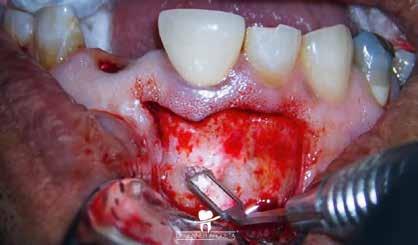

A következő kezelés elején helyi érzéstelenítést követően kofferdámot helyeztünk fel és az ideiglenes tömést eltávolítottuk. A pulpakamrát desztillált víz, és ED3D ultrahangos hegy segítségével aktivált 5,25%-os NaOCl oldattal megtisztítottuk. A következő cél az MB csatornák közti nyílás ED3D fejjel történő további kitágítása volt. Ezt követően észleltük, hogy az MB2 csatorna bemeneti nyílásának megfelelően strip perforáció alakult ki (8. ábra). Ekkor úgy döntöttem, hogy nem távolítok el további foganyagot, hanem újra elvégzem a Less-Prep Endo átöblítési protokollt. Ennek a hatékony átöblítési protokollnak az elvégzését követően még

potensebb folyadékáramlást lehetett észlelni az MB1 és MB2 csatornák között. Az MB1 és DB csatornákat 25/.07 Perfect Shape gépi tűvel, a P csatornát pedig 45/.04 Endostar E3 Azure gépi tűvel (Poldent) teljes munkahosszon feltágítottam. Végül az összes csatornát átöblítettem 5,25%-os NaOCl és 17%-os EDTA oldattal.

Az MB2 csatornát befecskendezéses technika alkalmazásával egy műgyanta alapú sealerrel töltöttem fel, míg a többi csatornát (MB, DB, P) ugyanezen sealerrel, de meleg guttapercha felhasználásával (continuous wave) töltöttem fel (9. ábra) . A perforációt ezt követően MTA-val (mineral trioxide aggregate) zártam (10. ábra) és kompozittal fedtem (11. ábra) . Több, excentrikus irányból készült periapikális röntgenfelvétel is készült. Ezeken egy további a mesialis gyökér apikális részén végigfutó sealer csíkot és a mesialis gyökér csúcsánál látható sealer puffot sikerült megfigyelni (12–13. ábra)

A mesialis gyökér megfelelő endodonciai ellátásának ellen őrzése céljából a pácienst egy kontroll CBCT-felvételre irányítottuk. A felvételen látható volt, hogy az MB2 csatornát teljes terjedelmében ki tudtuk tölteni a sealerrel, továbbá, hogy az apikális harmadban az MB1 és MB2 csatornák között egy keskeny összeköttetés található, valamint hogy az MB1 és MB2 gyökércsatorna különálló végződéssel rendelkezik (14. ábra) . A fogat kompozitfelépítéssel láttuk el, majd visszairányítottuk a beküldő orvosához. Csücsökborítást biztosító indirekt restaurátum készítését javasoltuk, illetve 6 hónap múlva kontrollvizsgálat céljából visszarendeltük magunkhoz. A 6 hónapos kontroll során készített CBCT-felvételen a gyökércsúcsok körül nem voltak gyulladásra utaló jelek. A fog teljesen panaszmentes volt és a Schneider membrán megvastagodását sem észleltük (15. a–b ábra.).